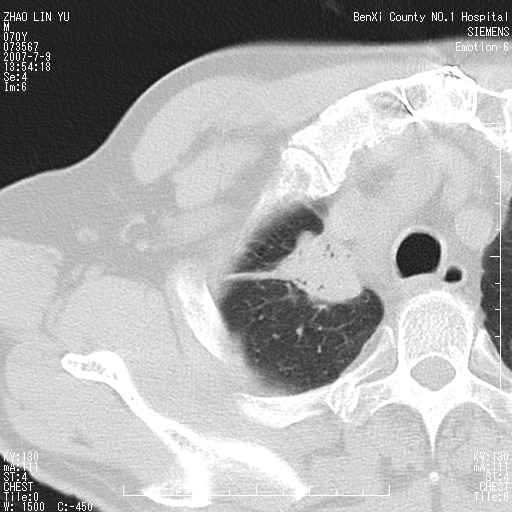

以下是引用王靖旗在2007-7-10 17:12:00的发言:[br] 男、70、咳嗽两个月,半年前换瓣手术,胸片未见异常,于昨天行x片发现右肺上野大片影,行ct扫描,这里是减薄图像,余肺正常。明天晚上会有增强扫描片,到时我会上传。[br][br] 冠状位请大家细看,应该是有意义的,[br][br] 请大家先看平扫发表意见。[br][br]

[br]冠状面[br]

以下是引用zhangzhongshou在2007-7-10 21:43:00的发言:[br]右肺上叶周围型肺癌,以孤立型细支气管肺泡癌可能性大。